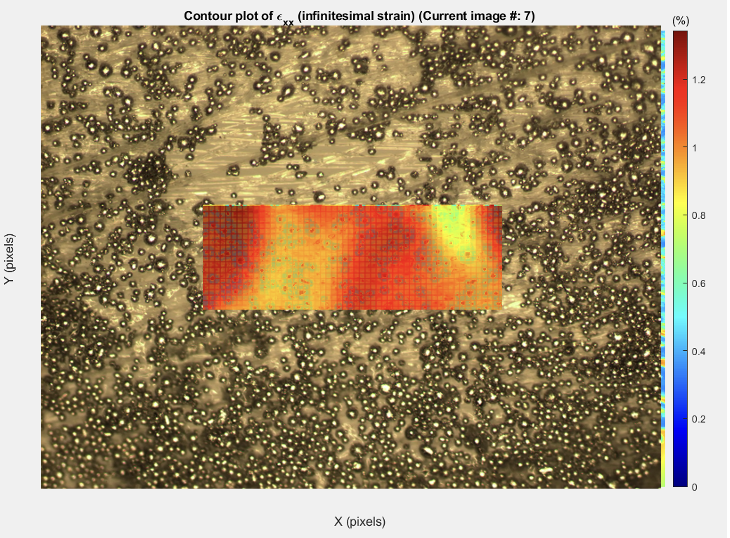

Masters work - validation of rotator cuff repair patch with stem cell implanted hydrogel.

Implanting cells into hydrogel and performing live/dead stain assay.